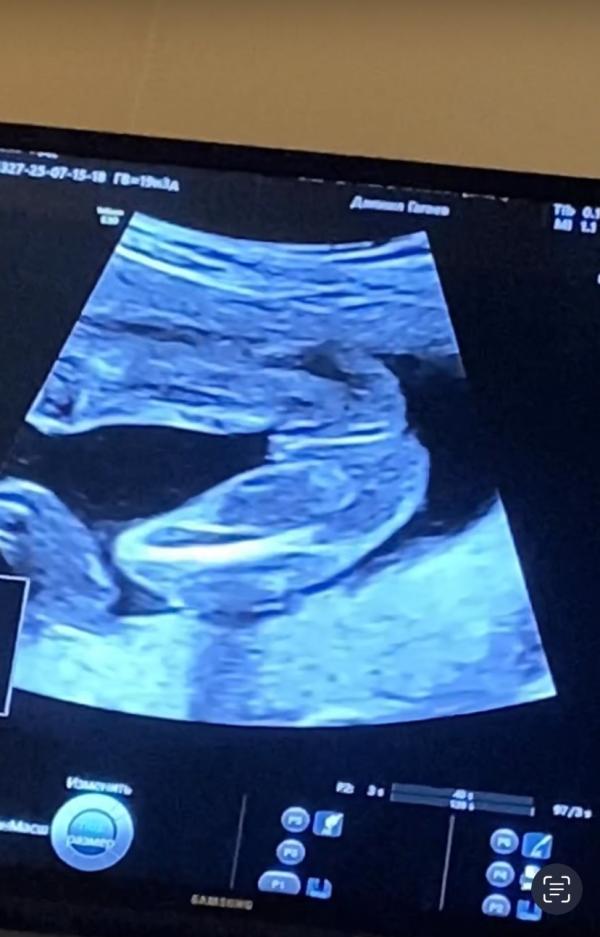

Ну вот и второй скрининг пройден😍 все отлично, подтвердили второй раз девчонку😍😍😍 Но нашли миому в матке, сказали наблюдать